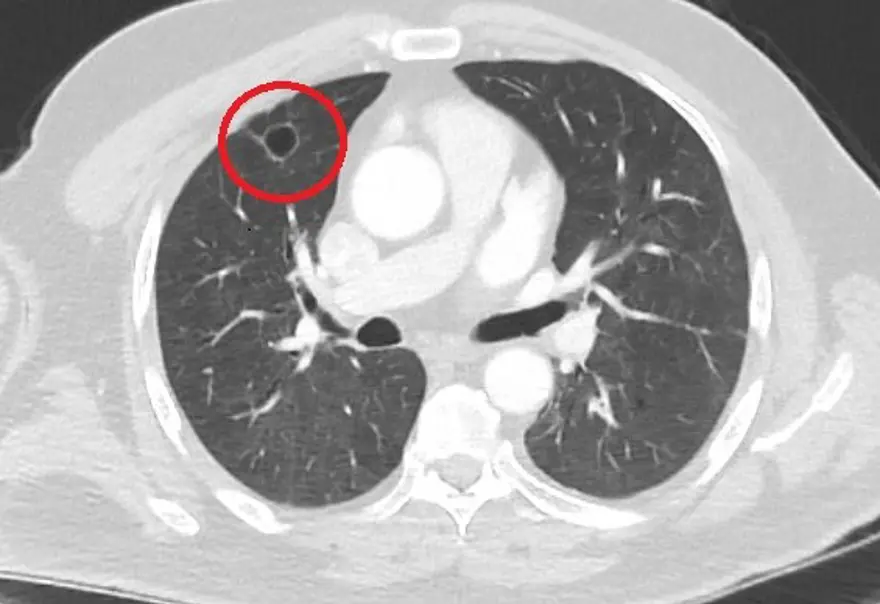

Kahramanmaraş'ta kent dışında çalışan N.T.'nin (52), göğüs ağrısı şikayetiyle gittiği hastanede çekilen tomografisinde sağ akciğerinde 4 santimetre çapında tümör tespit edildi.

Kanser olabileceği şüphesiyle yapılan ileri tetkikler sonrası N. T.'ye akciğer kanseri teşhisi kondu ve acil ameliyat kararı verildi. Bunun üzerine N.T., ameliyat için memleketi Kahramanmaraş'a geldi. Sütçü İmam Üniversitesi Sağlık Uygulama ve Araştırma Hastanesi Göğüs Cerrahi Anabilim Dalı Öğretim Üyesi Dr. Fatoş Kozanlı da tomografi ve test sonuçlarına göre N. T.'ye akciğer kanseri teşhisi koydu ve ameliyat yapılması gerektiğini söyledi.

Ameliyat öncesi N.T.'nin Covid-19 testi pozitif çıkınca operasyon ertelendi. Corona virüs tedavisine başlanan N.T.'nin son testi negatif çıktı. Dr. Fatoş Kozanlı, tedavi sonrası tomografisi çekilen N.T.'nin akciğerindeki tümörün yok olduğunu gördü. Kozanlı, N.T.'nin kendilerine başvurduğunda corona virüs belirtisi olmadığını ancak ameliyat öncesi PCR testi yaptıklarını söyledi. Corona virüs tedavisinin ardından ortaya çıkan sonucun kendisini de şaşırttığını belirten Kozanlı, şunları söyledi:

Ameliyatımızı 14 gün erteledik ve hastamıza corona virüs tedavisi uygulandı. Hasta 14'üncü gün tekrar bize başvurdu ve yapılan PCR testi negatif çıktı. Yeni bir tomografi çektik ve tümörün tamamen ortadan kalktığını gördük. Şimdi sonuç bilgilerinden başlangıca gittiğimizde, bu bir akciğer kanseri olsaydı, ortadan kalkması mümkün değildi. Başka bir patolojiye bağlı durum olsaydı, yine verdiğimiz tedaviyle ortadan kalkmasını çok beklemeyiz. Antiviral tedavisi verdik ve hastanın radyolojik bulguları neredeyse tamamen normale döndü. Hastaya bunu izah ettik, 'Dünya literatüründe hiç görülmeyen bir radyolojik bulgu' diyerek. Bu gördüğümüz manzara artık hastanın akciğer grafisinde yok, akciğer kanseri değil. "